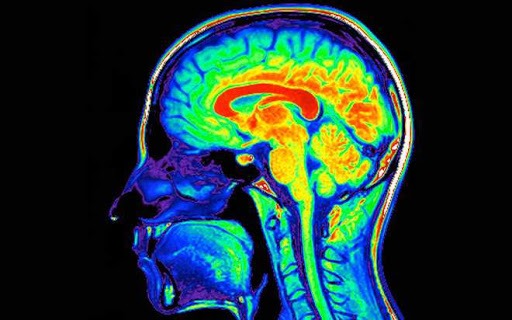

El abuso de **sustancias** es un problema global que afecta a millones de personas a diario. Desde el consumo de alcohol y drogas hasta el uso de medicamentos recetados de manera indebida, estas conductas pueden tener consecuencias devastadoras no solo en la vida social y emocional de las personas, sino también en su **cognición**. La función cognitiva comprende procesos esenciales como el pensamiento, la memoria, la atención y la toma de decisiones, los cuales son cruciales para el funcionamiento diario y la calidad de vida. Comprender cómo el abuso de sustancias interfiere con estos procesos es fundamental para abordar esta problemática y ayudar a quienes padecen estas adicciones.

Entender cómo el abuso de sustancias interfiere con la función cognitiva implica explorar los mecanismos biológicos y psicológicos en juego. A nivel neuroquímico, muchas de estas sustancias alteran la actividad de neurotransmisores críticos para la regulación del estado de ánimo, la motivación y el aprendizaje. Esto no solo altera la química del cerebro, sino que también interfiere con la conexión entre las neuronas, afectando la plasticidad sináptica, un proceso esencial para el aprendizaje y la memoria.

Adicionalmente, se ha descubierto que el **estrés** y la **ansiedad**, que a menudo coexisten con el abuso de sustancias, pueden intensificar el deterioro cognitivo. El estrés crónico provoca la liberación de hormonas como el cortisol, que a su vez puede afectar el hipocampo y la corteza prefrontal, áreas centrales para el funcionamiento cognitivo. El ciclo de uso y abuso de sustancias puede llevar a un deterioro cognitivo, que a su vez alimenta la necesidad de las sustancias como un mecanismo de afrontamiento.